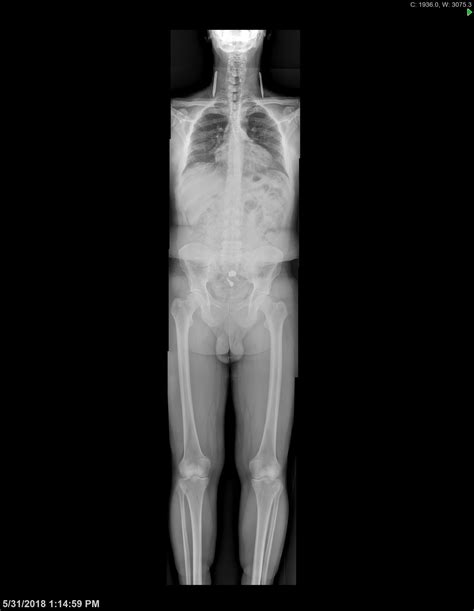

Musculoskeletal Radiology - University Diagnostic Medical Imaging